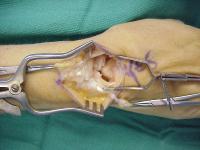

The retinaculum graft crosses over the capitate and is secured to a trough created in the dorsal distal scaphoid using a bone anchor.

Click for larger image

In this case, a dorsal capsulodesis was also secured to the same anchor attachment. Additionally, the original ligament remnant was unfurled from the lunate and reattached to the proximal scaphoid using a second bone anchor - a 3 point reconstruction.